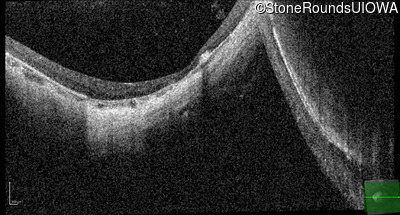

Optical Coherence Tomography - Left - 20/40 +1

Exemplar / OCT Stack

OCT Stack